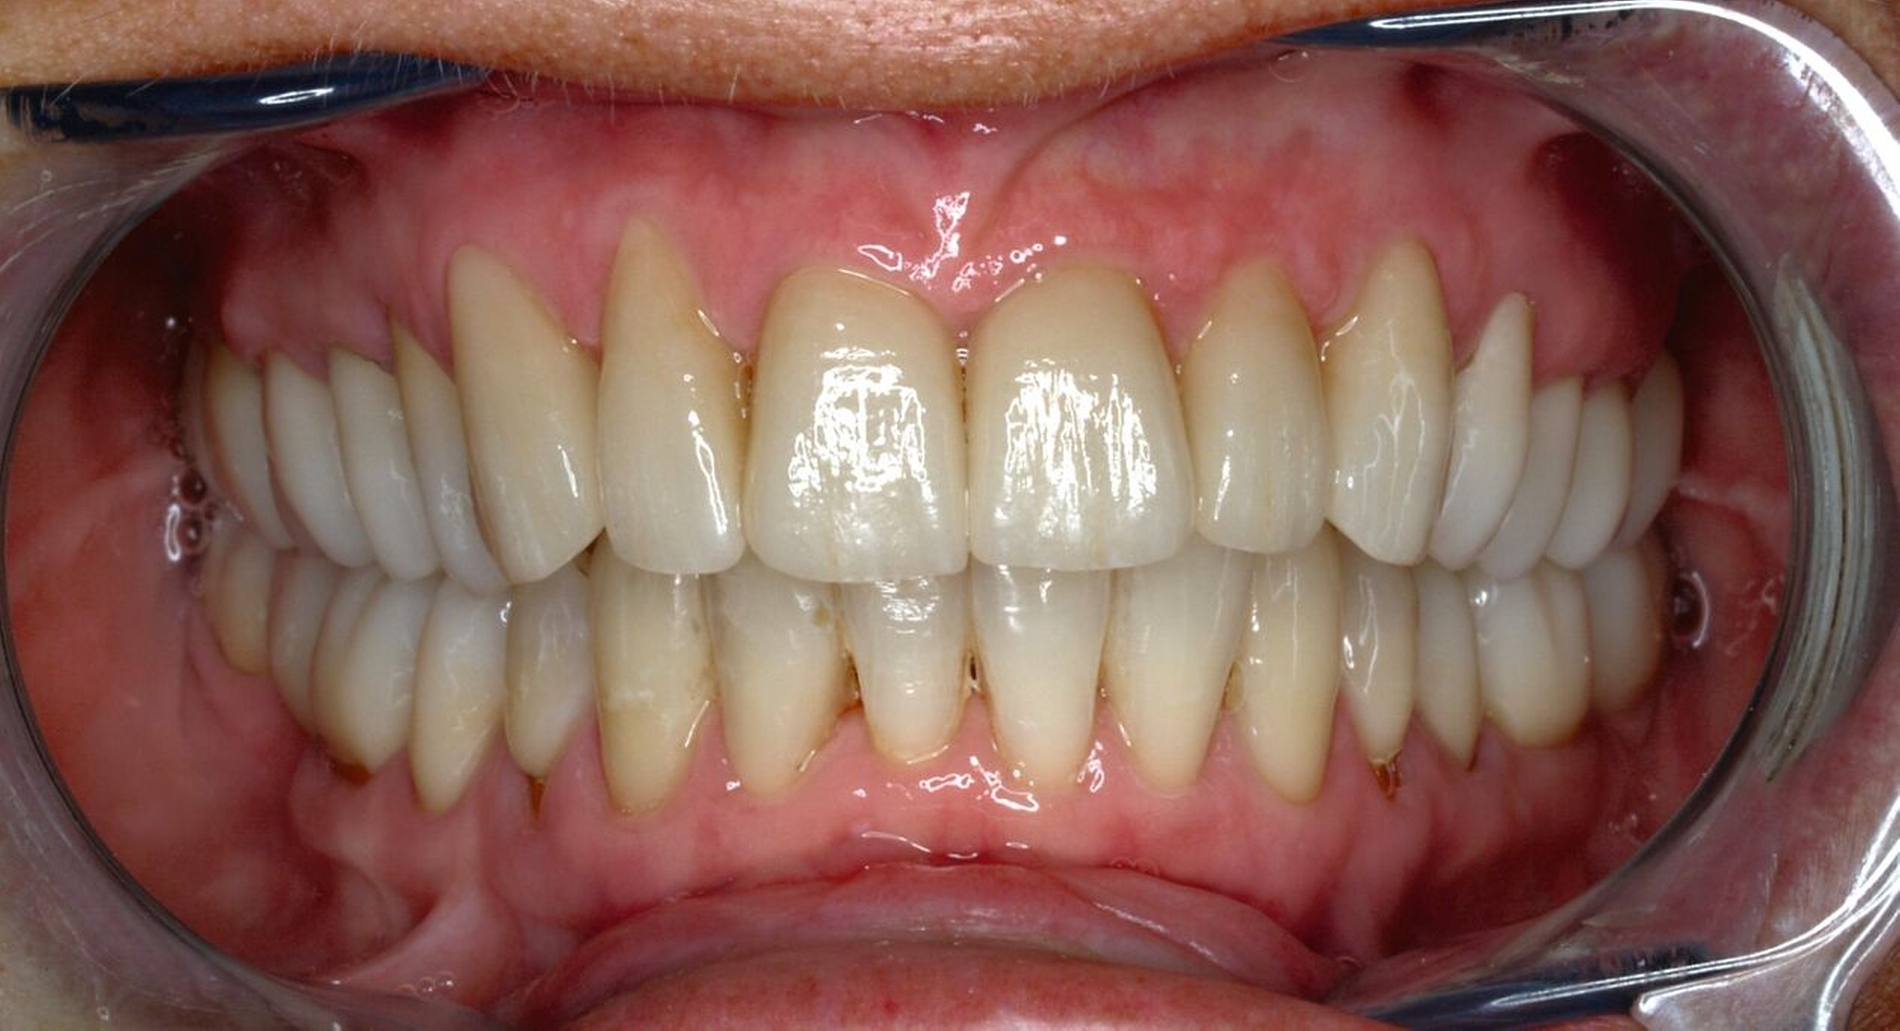

Klinisch zeigten sich diverse großflächig, mehrheitlich mit Amalgam gefüllte Seitenzähne, suffiziente endodontische Behandlungen an den Zähnen 16 und 14 sowie intakte Kronen an den Zähnen 16 und 48 (Abbildung 2). Ein Parodontaler Screening-Index (PSI) wurde erhoben (1-1-0-0-2-1), der stabile Verhältnisse nachwies. Das funktionelle CMD-Screening zeigte eine nicht-druckdolente Kaumuskulatur sowie eine uneingeschränkte Mundöffnung ohne Reiben und Knacken.

Tabelle 1 zeigt das entsprechende Befundschema mit den Taschentiefen mesial und distal, den Lockerungsgraden und den Sensibilitätsüberprüfungen mittels Kältespray (ViPr). Die Ruheschwebelage wurde mithilfe des Zielinsky-Zirkels auf 2 mm bestimmt. Die Nonokklusion im Seitenzahnbereich konnte auf circa 1,5 mm bemessen werden. Tabelle 2 spiegelt das entsprechende Okklusionsprotokoll wider. Das Okklusionsprofil wird auch in den Abbildungen 3a bis 3c deutlich.

Die anschließenden Verlaufskontrollen zeigten klinisch stabile Verhältnisse. Der prothetische Behandlungsaufwand betrug etwa acht Monate inklusive Planung, Begutachtung, Durchführung und Inkorporation des Zahnersatzes. In den Folgeterminen wurde der Patientin noch eine Aufbissschiene für den Unterkiefer eingegliedert, um Schäden durch etwaigen Schlafbruxismus vorzubeugen [Macedo et al., 2007]. Für die Nachsorge empfiehlt sich ein halbjährliches Kontrollintervall. Die erfolgte Okklusionskorrektur im Seitenzahnbereich wird in Abbildung 11 deutlich.